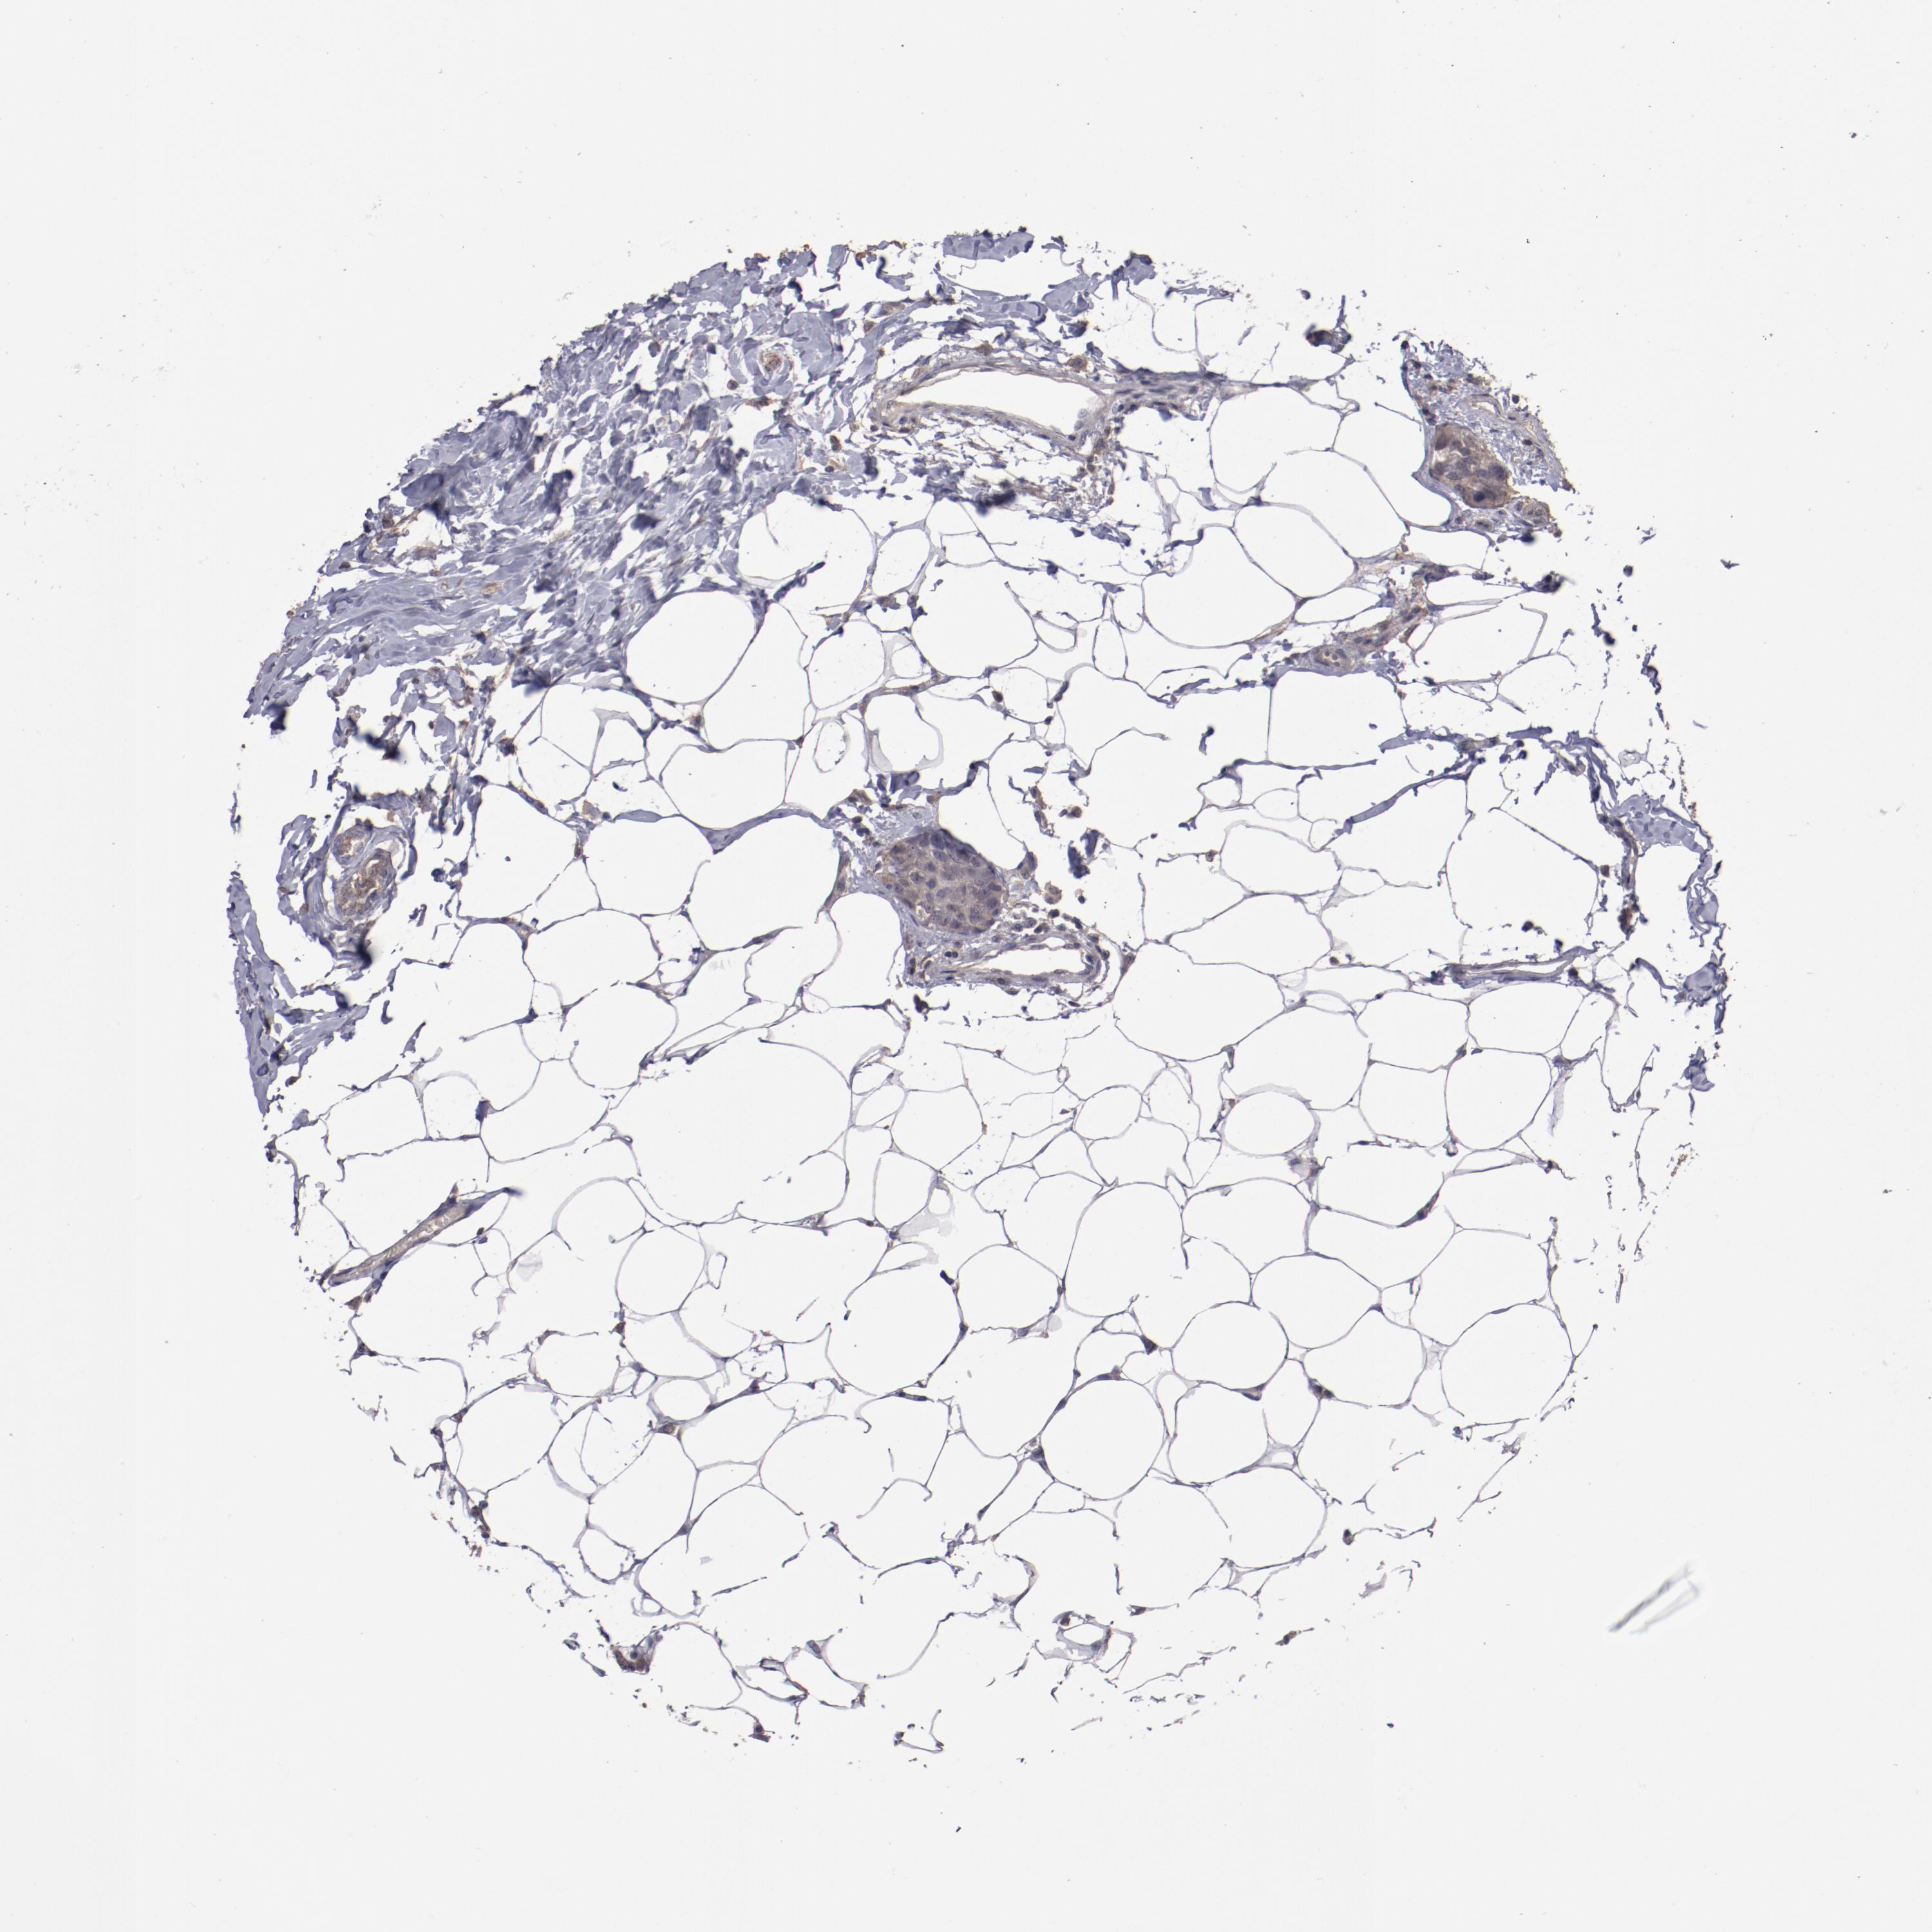

CANCER BREAST CANCER Show tissue menu

BRCA TCGA BRCA VALIDATION PROTEIN EXPRESSION